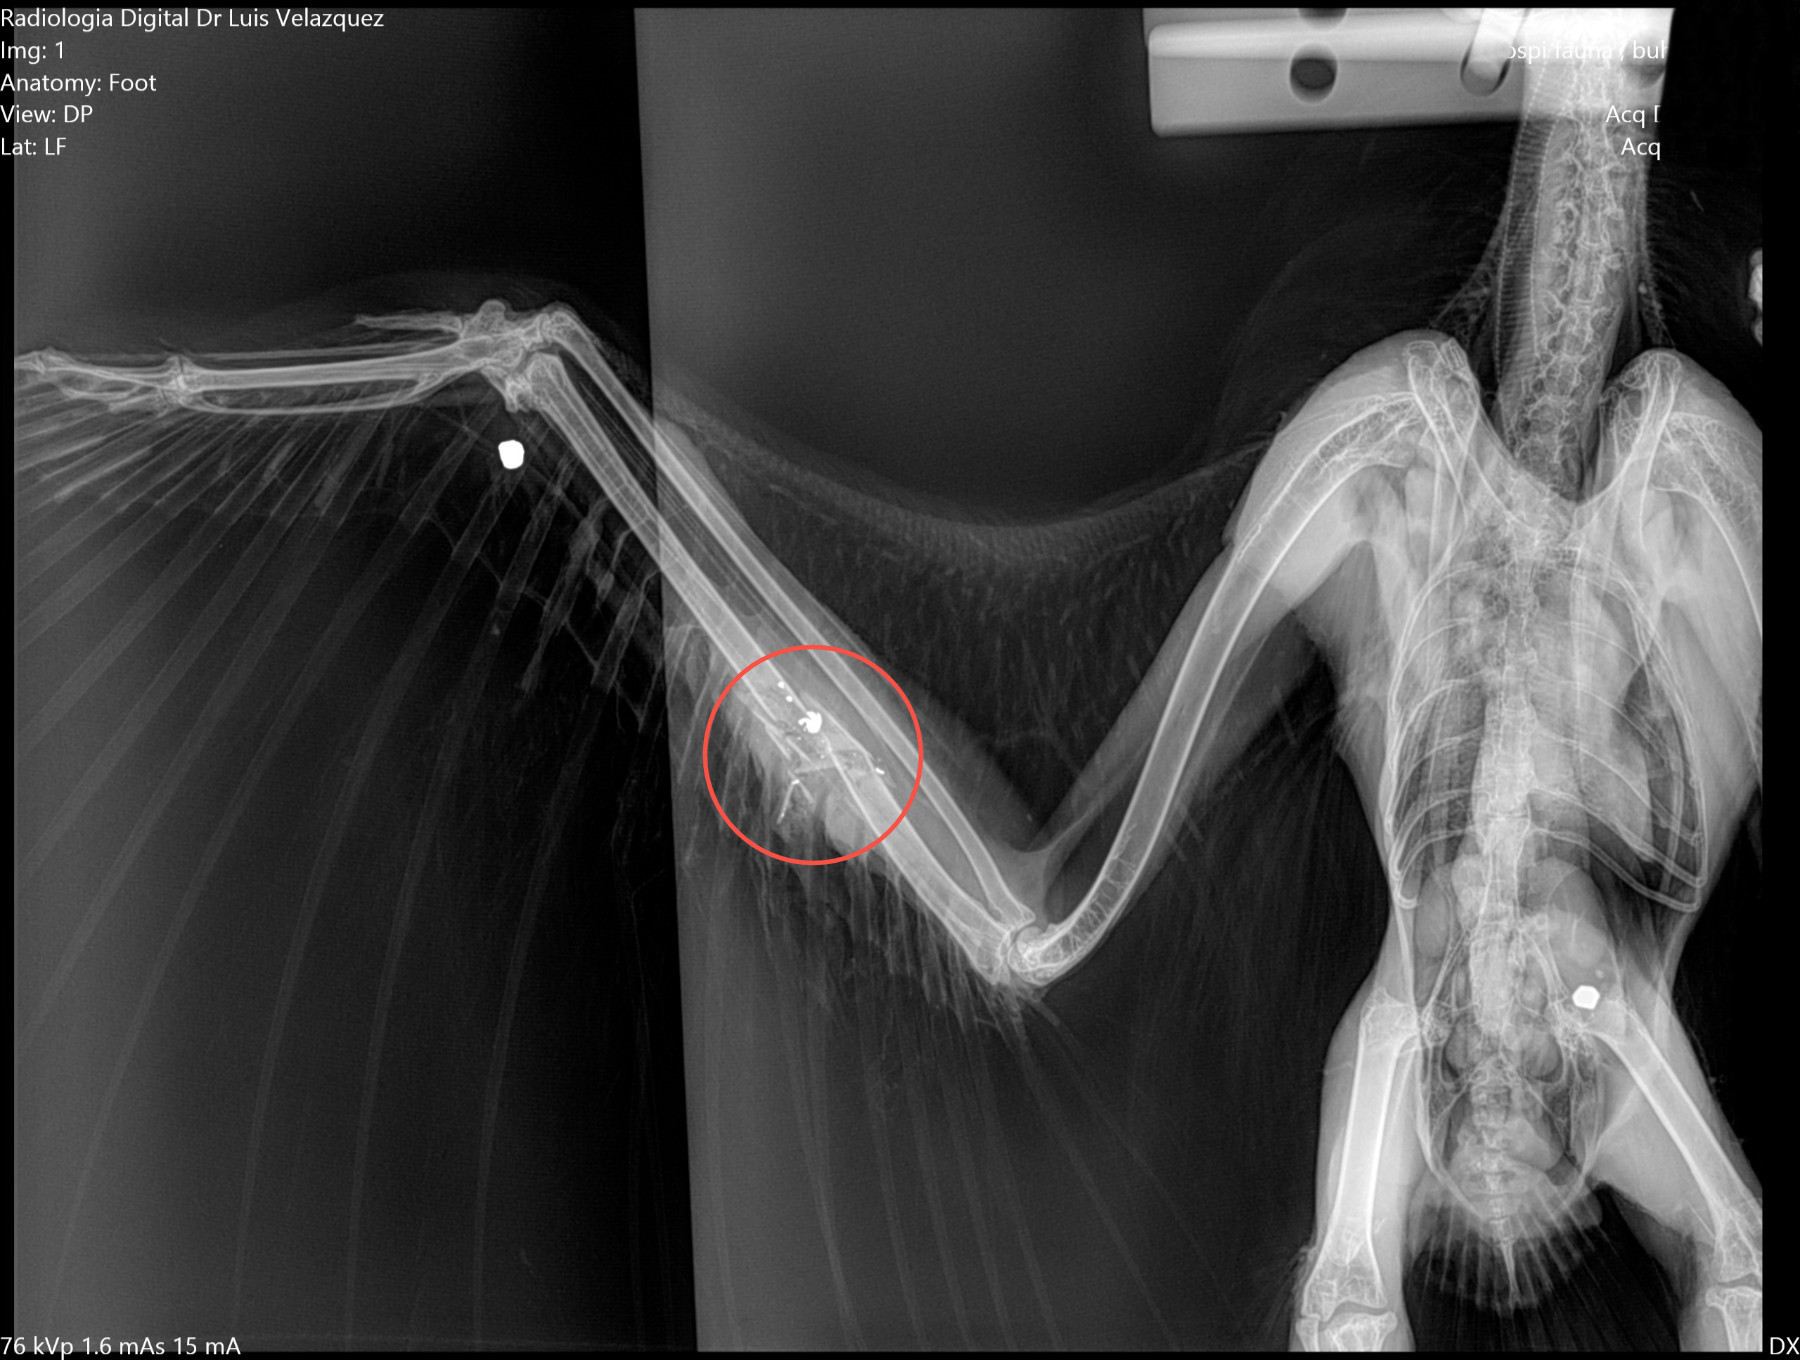

Radiología Digital como Herramienta Complementaria en el Dictamen de Bienes Muebles

Desde el descubrimiento de los rayos “X” y las placas radiográficas por Wilhelm Conrad Roentgen y su posterior difusión a través de la Asociación Físico médica de Wurzburg el 28 de diciembre de 1895, que fue la primera asociación que habló de los nuevos rayos que podían penetrar el cuerpo y fotografiar los huesos, ha habido muchos cambios tanto en la forma de obtener, procesar e incluso en la forma de visualizar, manejar y almacenar las placas radiográficas.